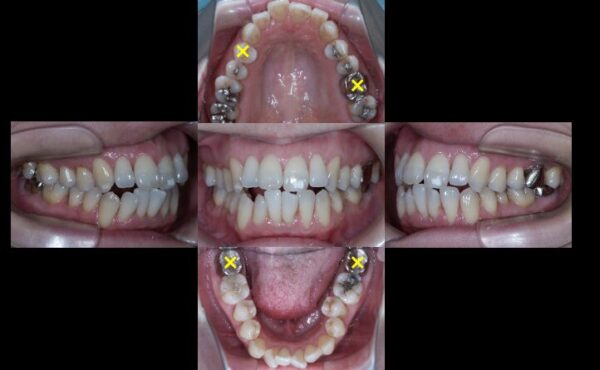

そこで、矯正治療が難しくなることを承知の上で、失活歯を抜歯し、状態の良い生活歯のみで咬み合わせを作る治療計画としました。

×印を付けたところを抜歯し、矯正治療を行う計画としました。

しかし、このまま単純に矯正をしたのでは歯は綺麗に並びません。そこで登場するのが「矯正用インプラントアンカー(TAD)」です。